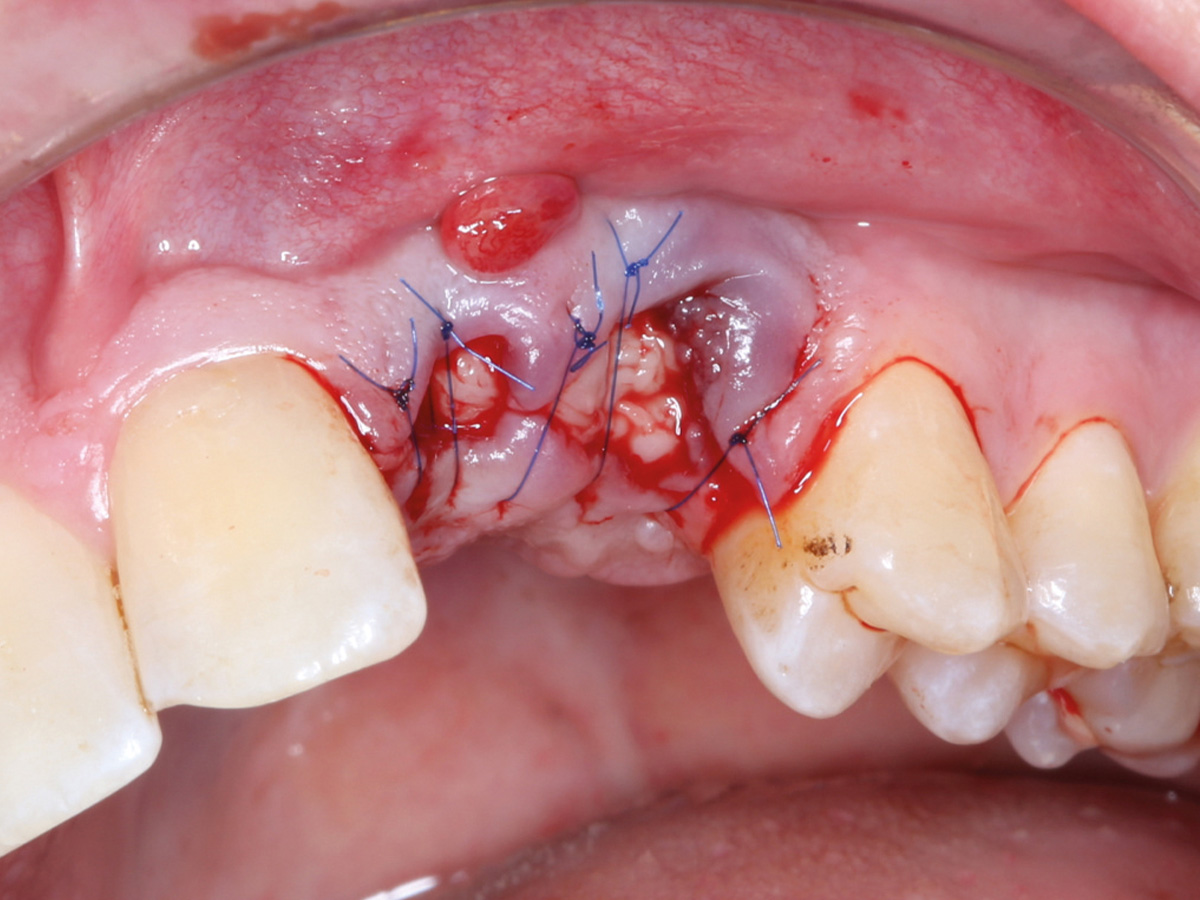

Abbildung 15

Nach mikrochirurgischem Nahtverschluss.